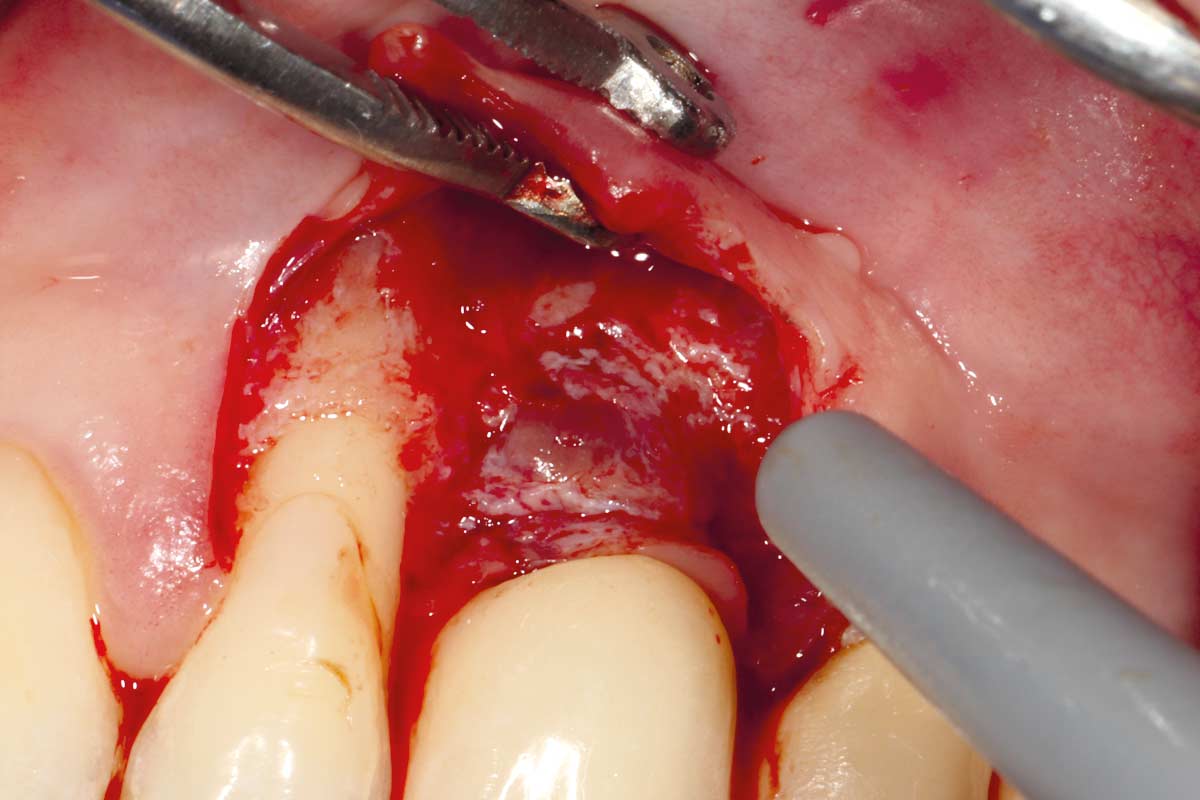

A patient presented with a peri-implant bone defect characterized by bone resorption compromising the stability and long-term prognosis of the implant. To re-establish sufficient bone volume and ensure implant longevity, a regenerative surgical intervention was performed using a guided bone regeneration (GBR) approach. The treatment featured cerabone® plus for grafting, complemented by the Shield Technique using fully resorbable magnesium-based NOVAMag® SHIELD to guide bone regeneration.